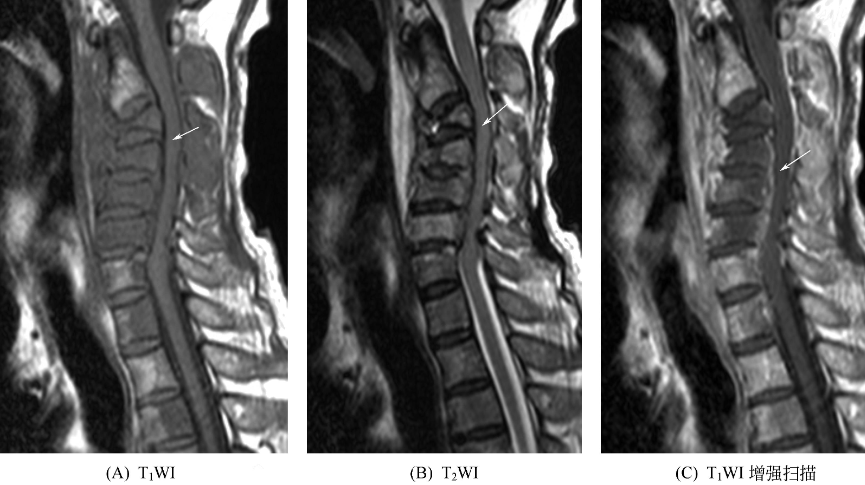

转移性骨肿瘤可单发或多发,以多发常见,多见于躯干骨,尤其是脊柱,长骨通常以膝、肘以上好发,其远侧少见。最好发于红骨髓区或骨松质内,表现为形态多样的异常信号影。溶骨性病灶表现为T1WI呈低信号,T2WI、抑脂序列为高信号,增强后有强化。成骨性病灶在T1WI和T2WI上均为低信号,增强后可为轻度强化或无强化。转移性骨肿瘤可伴有软组织肿块,极少有骨膜反应,如合并病理性骨折则可能会有骨膜反应,呈T1WI、T2WI骨皮质外均匀或不均匀低信号长条状影。少数扁骨、骨干囊状膨胀性转移性骨肿瘤,T1WI呈等信号或不均匀信号,T2WI为高信号,周边可见低信号环绕,增强后有强化。脊椎广泛受侵常易并发病理性压缩性骨折,椎旁多可见局限性对称性软组织肿块。椎间隙正常。椎弓根多受侵蚀、破坏(图8)。

图8 转移性骨肿瘤颈3~颈6椎体明显变扁,椎体及附件呈弥漫稍长T1稍长T2信号改变,附件周围可见软组织肿块,增强扫描呈轻度强化。各椎间隙正常,相应节段脊髓受压,呈稍长T2信号改变。颈7、胸1~胸4后半椎体亦见稍长T1稍长T2信号改变,增强扫描轻度强化。